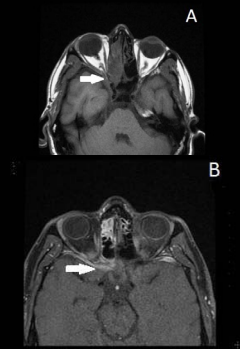

Cranial magnetic resonans angiography and orbital MRI examinations were fulfilled to exclude potential cavernous sinus thrombosis and orbital involvement for the patient. Soft tissues signals compressing rectus muscle, optic nerve, cavernous sinus and optic vein softly were exist during cranial MRI. Contrast involvement depending on infection effects optic nerve, surrounding soft tissue, ethmoid mucosa and around cavernous sinus on the right side was observed during T1-weighted MRI sequence after contrast material (Figure 2 A,B).

Contrast involvement depending on infection effects optic nerve, surrounding soft tissue, ethmoid mucosa and around cavernous sinus on the right side was observed during T1-weighted MRI sequence after contrast material.

Figure 2: Contrast involvement depending on infection effects optic nerve, surrounding soft tissue, ethmoid mucosa and around cavernous sinus on the right side was observed during T1-weighted MRI sequence after contrast material.

Cavernous sinus thrombosis was not occurred.